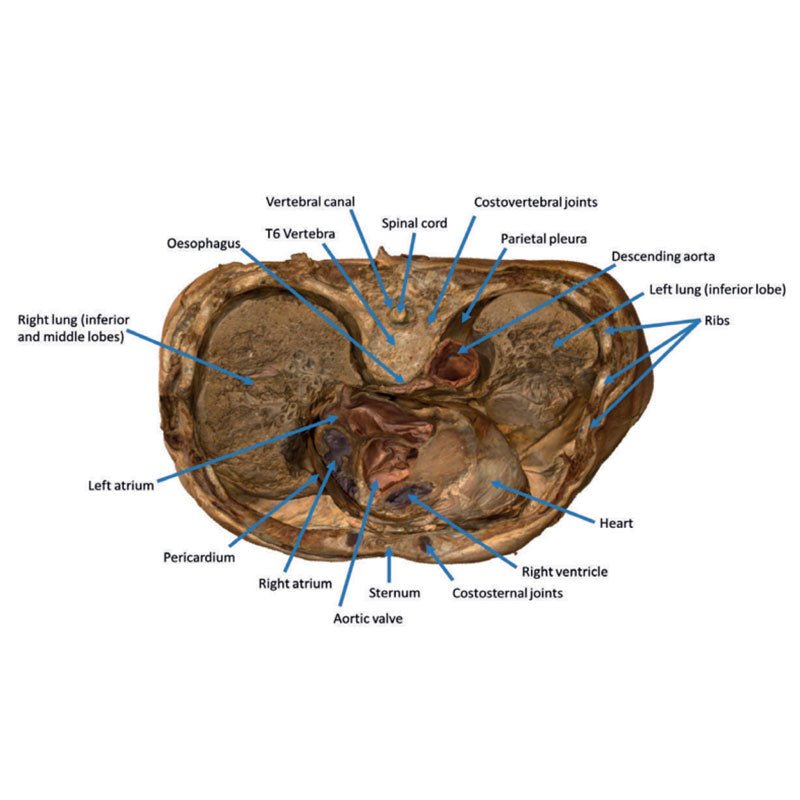

3D Printed Thoracic Cross Section at T6

This model is a cross-section of the thorax at the level of the T6 vertebra. Beginning posteromedially at the spinal

cord within the vertebral canal, then moving radially, the costovertebral joints of the 6th ribs are visible,

followed by several other ribs around the margin of the thoracic cavity, a pair of which unite anteriorly with the

sternum via the costosternal joints. Additionally, the oesophagus and descending aorta are visible anterior and

lateral to the T6 vertebral body, respectively.

Inside the plural space, lined by the parietal pleura,

reside the

inferior and middle lobes of the right lung and the inferior lobe of the left lung.

In the middle

mediastinum the

heart, within the pericardium, is transacted to reveal the left atrium posteriorly, then moving clockwise, the

aortic valve, right ventricle and the right atrium.